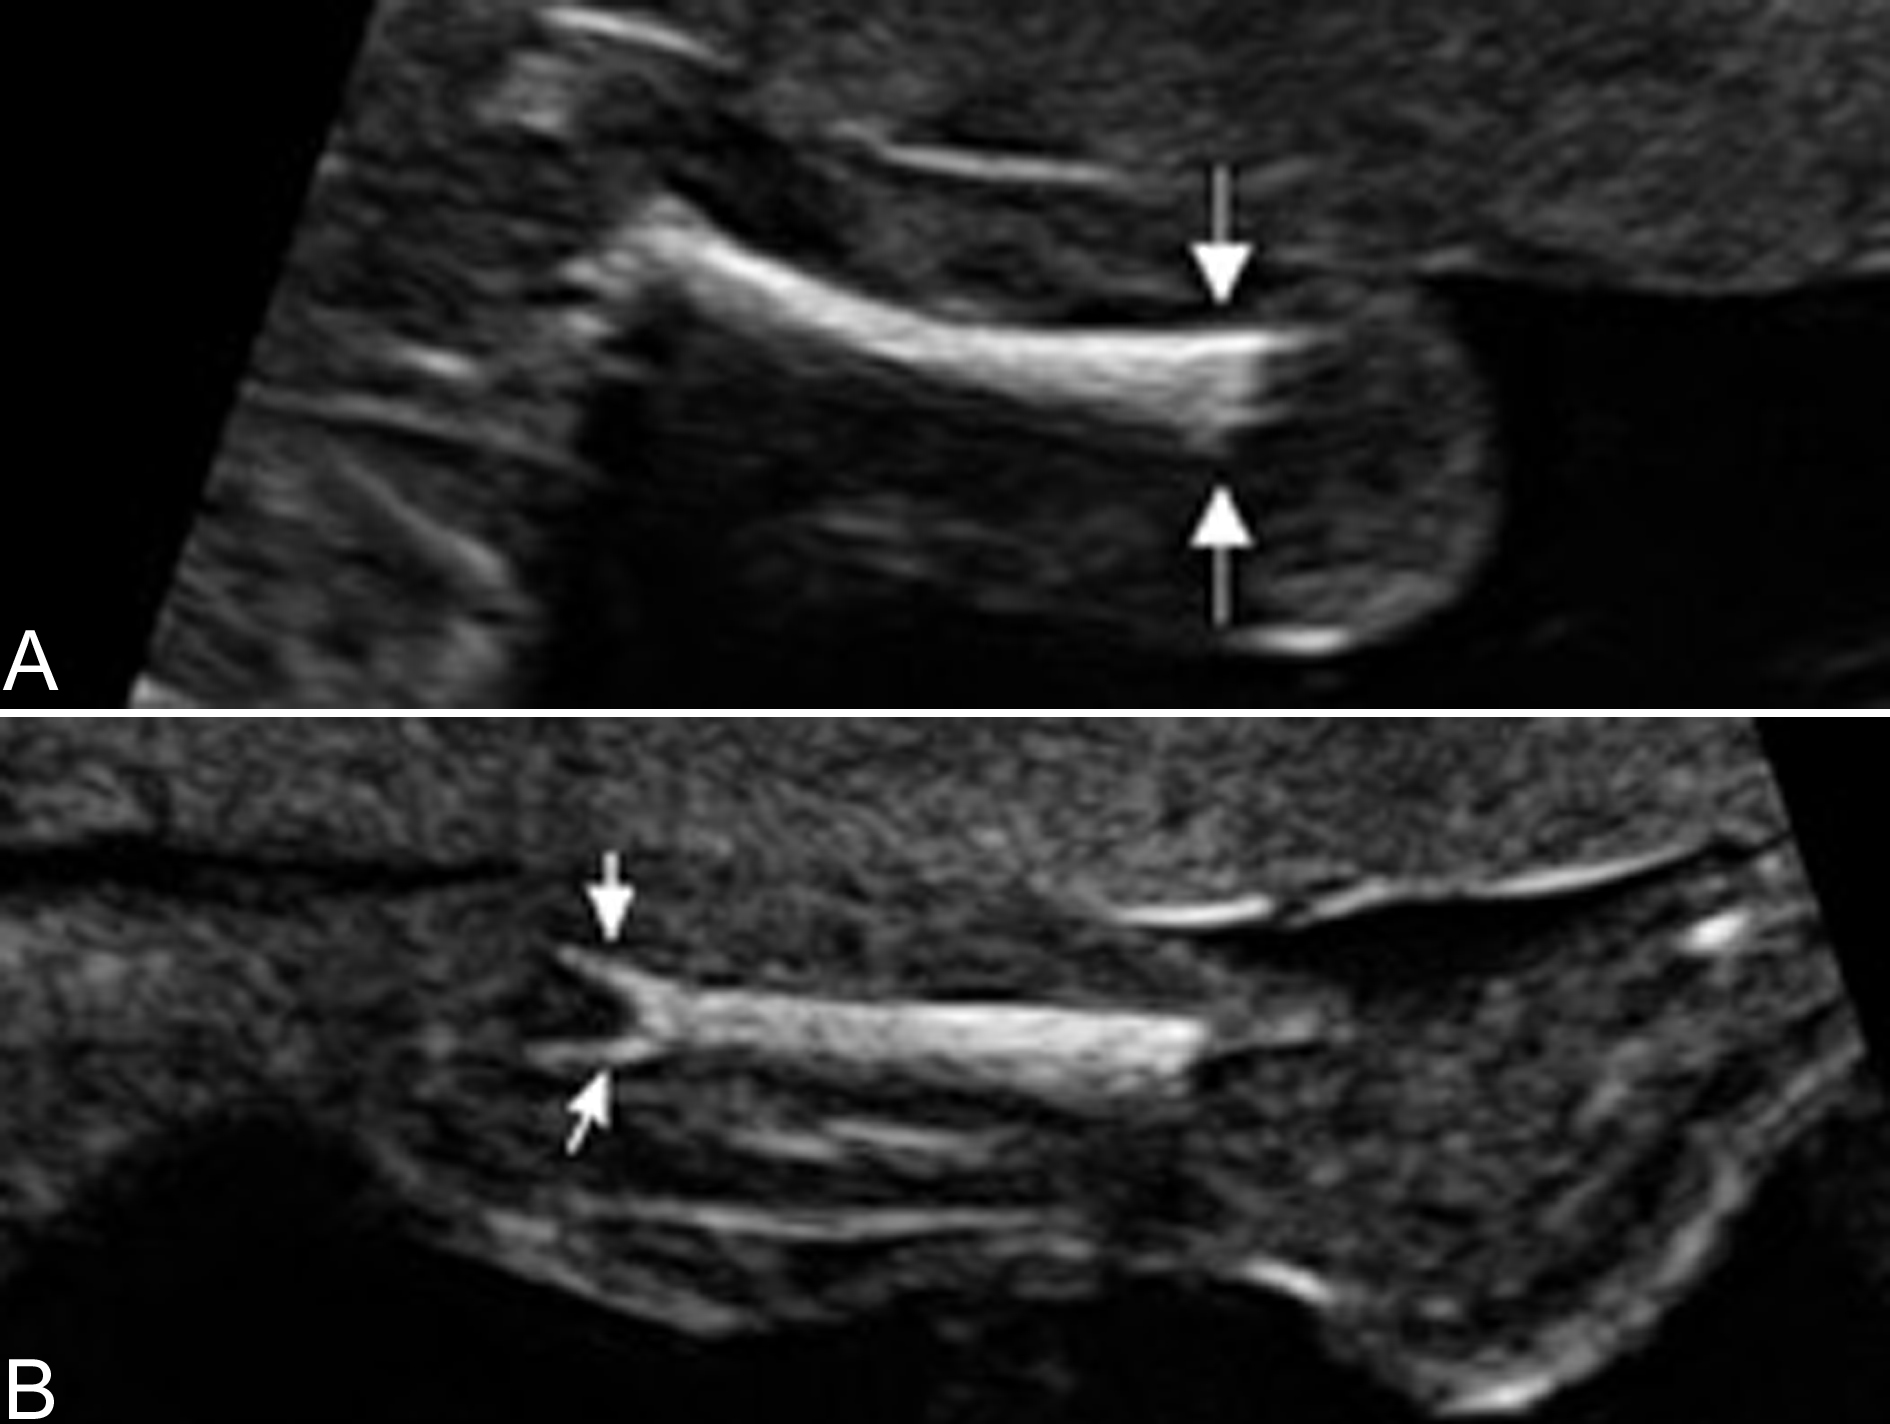

(2)长骨弯曲程度:与长骨的骨化程度评估一样,长骨弯曲程度的评估缺乏客观指标,需要依靠超声检查异常的经验区分正常和异常(图3)。很多骨的发育异常都有长骨的弯曲畸形,如致死性侏儒、肢体屈曲症等。

图3胎儿股骨弯曲畸形:呈电话柄样改变(箭头)(B为X线摄片)